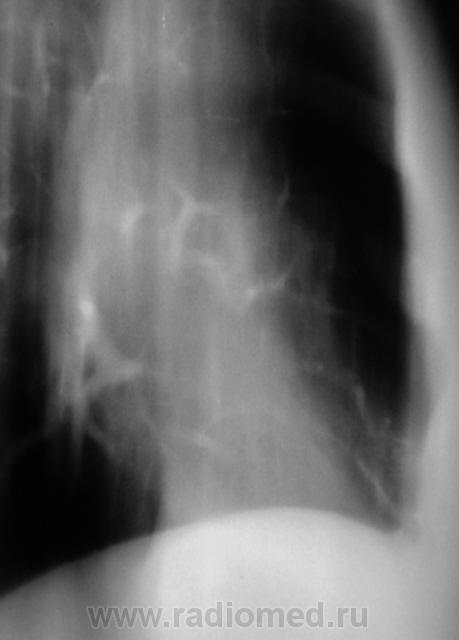

Еще контроль через 1 месяц.